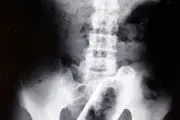

• مرد جوان بطری بزرگ شیشه‌ای را قورت داد+ عکس

مرد جوان بطری بزرگ شیشه‌ای را قورت داد+ عکس

بطری شیشه ای چطور به داخل شکم این مرد راه یافته بود برای پزشکان و خود بیمار هم سوال بود ، تصاویری که انتشارش در فضای مجازی با موجی از واکنش ها همراه بود.